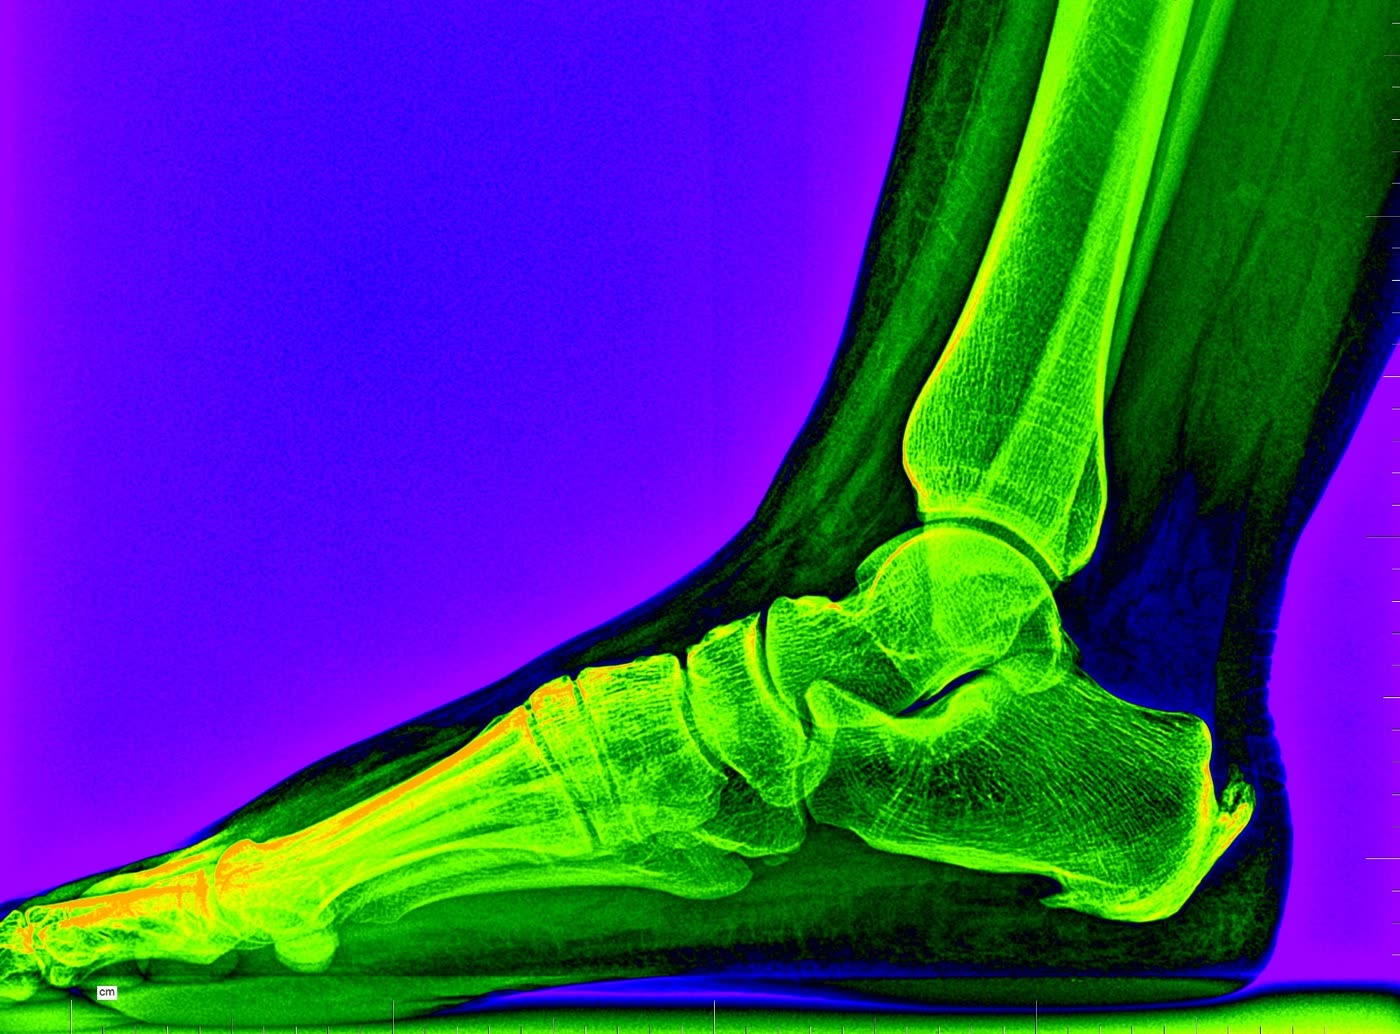

Radiología digital

Disponemos de radiología digital en consulta para el estudio de la estructura ósea del pie y tobillo. Imprescindible en el diagnóstico de fracturas, deformidades como el hallux valgus (juanete), pie plano o cavo estructural, artritis, etc. Las imágenes son inmediatas, de alta resolución y con mínima radiación.

Hallux valgus Fracturas Artritis Deformidades

Radiografía pie — proyección lateral Radiografía pie — proyección dorso-plantar

Arrastra para comparar · Radiología digital en consulta